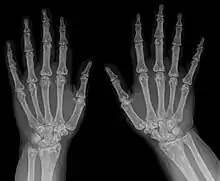

Osteopoikilosis results in multiple enostoses. | |

An enostosis is a small area of compact bone within the cancellous bone.[1][2] They are commonly seen as an incidental finding on radiographs or CT scans. They are typically very small and do not cause any symptoms.[3] Their radiodensity is generally similar to cortical bone.[4] No treatment is necessary. Multiple enostoses are present in osteopoikilosis.[5]